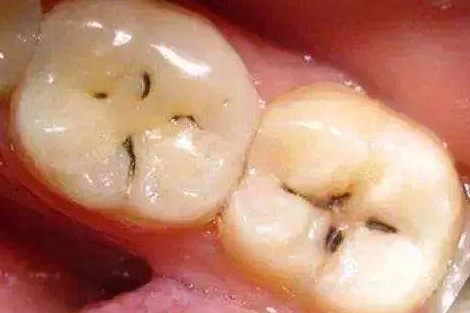

ЁЁЁЁбРвНЫЕЃК“ШЃВЁЪЧгЩвдЯИОњЮЊжїЕФЖрвђЫиЕМжТЕФбРГнгВзщжЏЗЂЩњТ§адНјааадЦЦЛЕЕФвЛжжМВВЁЁЃвбОПЊЪМЧГШЃМДбРгджЪШЃЃЌашвЊзівЉЮяжЮСЦЛђГфЬюжЮСЦЁЃ

ЁЁЁЁбРвНШДЫЕЃК“етЪБВЁБфвбОЦЦЛЕЕНбРБОжЪЧГВуСЫЃЌбРГнвбОгаШЃЖДаЮГЩЃЌЖдЫсЬ№ЪГЮяУєИаЃЌашвЊзіГфЬюжЮСЦЁЃ”

ЁЁЁЁбРвНИцНыЫЕЃК“ВЁБфвбОЦЦЛЕЕНСЫбРБОжЪЩюВуЃЌбРГнгаНЯЩюЕФШЃЖДЃЌЮТЖШДЬМЄЃЌЛЏбЇДЬМЄвдМАЪГЮяНјШыШЃЖДЪБОљв§Ц№ЬлЭДЃЌДЫЪБЃЌМАЪБзіГфЬюжЮСЦЕФЛАЛЙРДЕУМАБЃзЁбРЫшЁЃ”